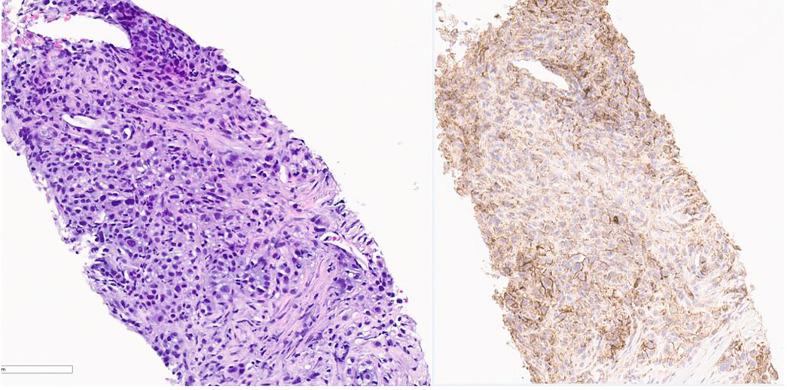

The incidence of cervical cancer has decreased in recent years due to widespread vaccination and routine screenings. It can be treated successfully, and the prognosis is also excellent if detected early. However, the 5-year survival rate for patients with stage IV cervical cancer is only 17% even with aggressive systemic chemotherapy. With the Food and Drug Administration (FDA)'s approval of immunotherapy, the prognosis has improved. We present a patient with stage IV cervical cancer who could not tolerate platinum-based chemotherapy and bevacizumab, so she was started on an immune checkpoint inhibitor, as her tumor was 100% programmed cell death ligand-1 (PD-L1) positive. She survived more than 2 years since the diagnosis of stage IV cervical cancer without any significant side effects. Based on our patient's response, the use of immune checkpoint inhibitors as a single agent needs further research and probably can be considered in patients with stage 4 cervical cancer who cannot tolerate standard chemotherapy.